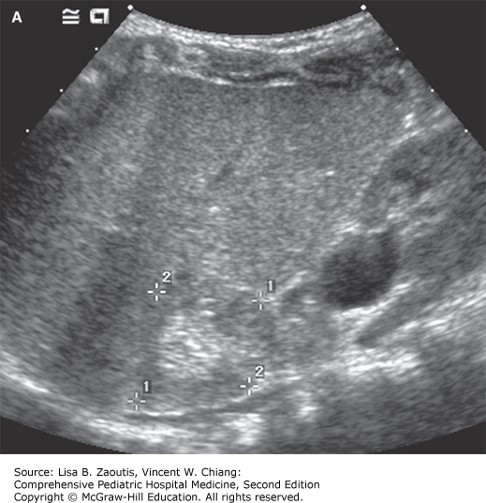

The correct answer is “C.” Hypocalcemia in the setting of end-stage renal disease (ESRD) is most commonly associated with hyperphosphatemia and vitamin D deficiency. Control of hyperphosphatemia will generally normalize hypocalcemia by use of phosphate binders, low-phosphate diet, renal replacement therapy (dialysis), or a combination of these. Unless there is symptomatic hypocalcemia, acute calcium repletion is not warranted. Renal ultrasound will be instrumental in diagnosing the etiology of his renal failure. In this setting with a well-grown adolescent, chronic kidney disease (CKD) with a history of polyuria and bland urine may be consistent with a diagnosis of juvenile nephronophthisis, with typical features of normal but diffusely echogenic kidneys. The choice of maintenance IV fluids without potassium is optimal given mild to moderate hyperkalemia, and he is not oliguric with signs of hypervolemia. Similarly, a low-phosphate diet and potassium dietary restrictions would be optimal until renal replacement therapy is provided. As the patient is clinically stable with signs of ESRD, consulting pediatric nephrology and transferring him to begin renal replacement therapy is appropriate.